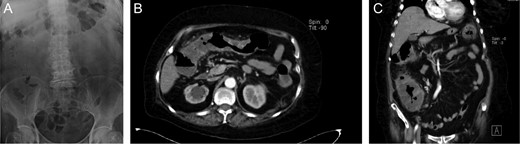

On clinical examination a tachycardic, febrile and dehydrated patient with diffuse abdominal tenderness and guarding was encountered. After proper reanimation, laboratory exams were requested. Complete blood count and abdominal x-ray appeared normal (Fig. 1A), yet stool examination revealed multiples cysts and trophozoites of E. histolytica. Since pain persisted and became more intense, a contrast-enhanced abdominal computed tomography revealed the presence of diffuse colonic mural thickening and enhancement (Fig. 1B) along with pericolonic stranding. No free air under the diaphragm was found (Fig. 1C).

(A) Abdominal x-ray, without signs of pneumoperitoneum. (B) Abdominal CT, with diffuse colonic mural thickening and enhancement. (C) Abdominal CT with pericolonic stranding.